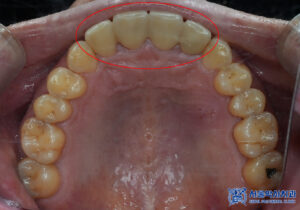

육안으로 확인해 보았을 땐

특별한 이상이 없어

파노라마를 촬영해 보기로 하였습니다.